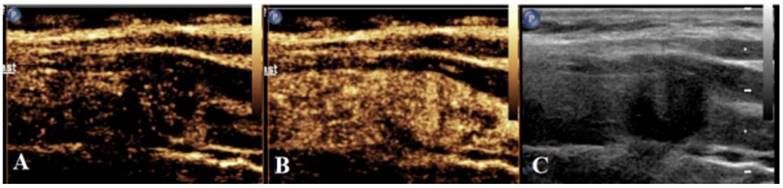

CEUS method

After real-time SWE, CEUS was conducted as follows. The elbow vein was injected with contrast agent (2.4 mL; Sonova, Switzerland), followed by tube flushing with 5 mL of normal saline. Next, dynamic images were saved after starting the timer. CEUS was ended following continuous observation for a minimum of 90 s (Figure 3). The time-intensity curve (TIC) was plotted using contrast analysis software, for the purpose of recording time to peak (TTP), rising time (RT), area under TIC (AUCt) and peak intensity (PI).

Figure 3

Schematic diagram of centrifugal enhancement of nodules in CEUS mode. (a) At 10 s after contrast agent injection, enhancement is firstly found in the center of nodules, followed by the periphery. (b) At 17 s after contrast agent injection, nodules display uneven iso-high enhancement. (c) Two-dimensional ultrasonic diagram of nodules during CEUS dual imaging.